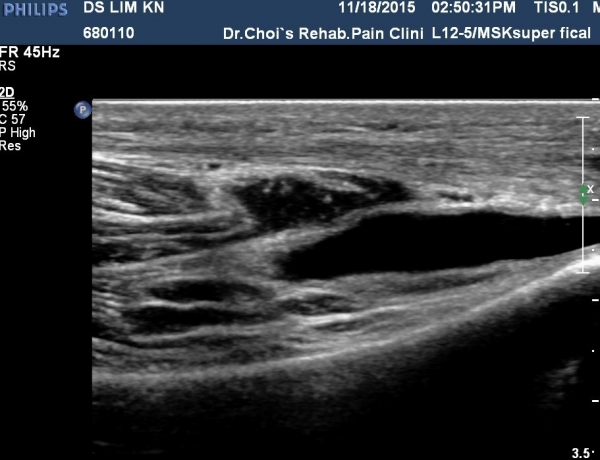

¹«¸­ ¿ÜÃø Á¾´Ü¸é°Ë»ç¿¡¼­ °üÀý³» ¼ö¾×Àú·ù°¡ °üÂûµÊ(»çÁø 1, 2).